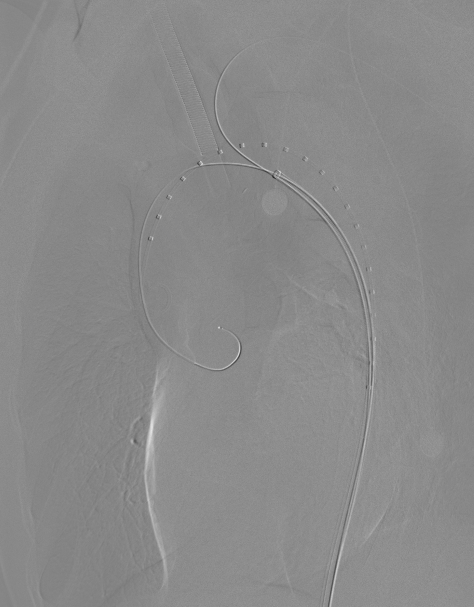

手术过程

1、穿刺患者左侧颈动脉与右股动脉,并在左颈动脉置入7F的穿刺鞘后,导入软导丝,自上而下地探索真腔,在穿出右股动脉后,从左股动脉导入9F长鞘至降主动脉,先后在长鞘内交换导丝为超硬导丝,分支导丝和造影导管导丝,下撤长鞘后,上推黄金标记导管至升主动脉造影;

动脉长鞘怎么置入【弓部重建直通车】真腔难觅,另辟蹊径|潍坊市人民医院血管外科运用Castor®支架结合长鞘建立导丝通路治疗主动脉夹层两例_https://www.jmylbn.com_新闻资讯_第15张

术前造影

2、上推支架,助手配合牵拉分支导丝,使分支支架进入LCCA;

动脉长鞘怎么置入【弓部重建直通车】真腔难觅,另辟蹊径|潍坊市人民医院血管外科运用Castor®支架结合长鞘建立导丝通路治疗主动脉夹层两例_https://www.jmylbn.com_新闻资讯_第16张

上推支架